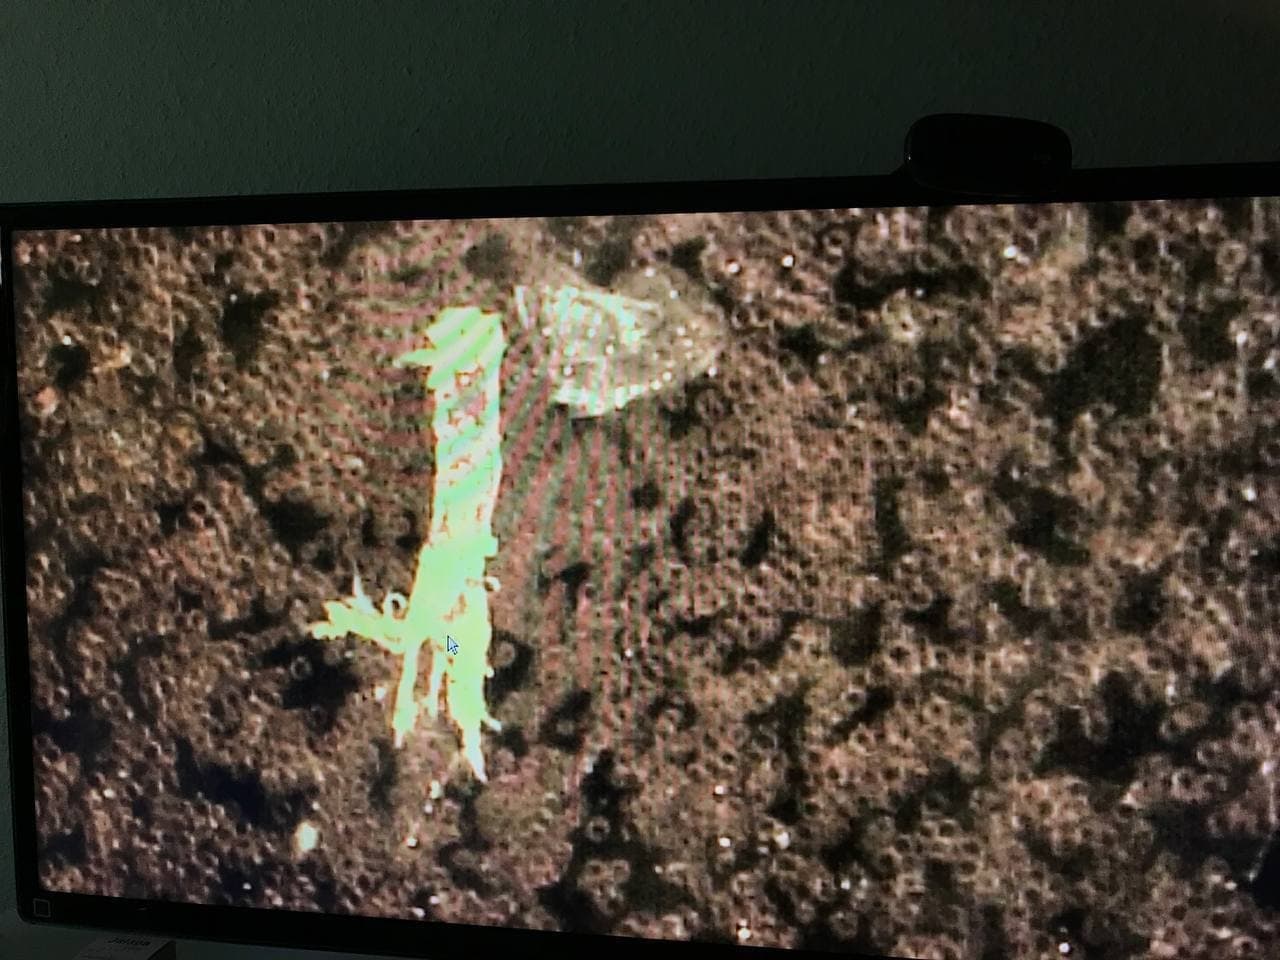

GENgeimpfte Menschen mit schweren

Nebenwirkungen in Südafrika 6.10.2021: Gestapelte

Blutzellen und schwarze Strukturen im Blut - Ärztin Zandre

Botha:

Purer Horror: Arzt entdeckt mysteriöse „schwarze

Strukturen“ im Blut von geimpften Patienten

https://uncutnews.ch/purer-horror-arzt-entdeckt-mysterioese-schwarze-strukturen-im-blut-von-geimpften-patienten/

Video auf Rumble (4.Okt.2021): https://rumble.com/vnbgal-never-before-seen-blood-doctor-reveals-horrific-findings-after-examining-vi.html

Video auf Bitchute (6.Okt.2021): https://www.bitchute.com/video/Sffxfn2Q7RGA/

Video auf VK (7.Okt. 2021): https://vk.com/video472868156_456239639

Video auf GloriaTV (5.Okt.2021): https://gloria.tv/post/CYb3Qraejiiy2SRLNkusqEjaC

Immer mehr Patienten der südafrikanischen Ärztin Zandre

Botha leiden nach der Corona-Impfung unter

Nebenwirkungen. Dazu gehören Thrombosen, Embolien,

kognitive Probleme, Nervenschmerzen und Kurzatmigkeit.

Sie beschloss, das Blut ihrer Patienten unter dem

Mikroskop zu untersuchen und war schockiert.

Die roten Blutkörperchen der Geimpften seien bis zur

Unkenntlichkeit deformiert, sagte Dr. Botha in der Stew

Peters Show. „Das habe ich noch nie gesehen. Ich war

schockiert“, sagte die Ärztin, die seit 15 Jahren in

diesem Bereich tätig ist.

Schwarze Strukturen

Außerdem fand sie bei allen geimpften Patienten mit

Symptomen „schwarze Strukturen“ im Blut. „Ich war sehr

schockiert“, sagte sie.

Botha gelang es auch, einen Janssen-Impfstoff in die

Hände zu bekommen und dessen Inhalt unter dem Mikroskop zu

untersuchen. „Ich war sehr schockiert, denn was ich im

Blut meiner Patienten fand, war auch im Impfstoff

enthalten“, sagte sie. Sie bezog sich auf die schwarze

Substanz, die aus zahlreichen Scheiben mit Löchern

besteht.

Der Arzt entdeckte auch seltsame rechteckige Strukturen

in dem Impfstoff. „Ich weine, wenn ich solche Dinge sehe.

Ich weine, wenn diese Patienten reinkommen“. Sie sagte,

einer ihrer Patienten habe innerhalb von fünf Stunden nach

der Impfung acht Herzinfarkte erlitten und liege nun auf

der Intensivstation. „Ich hoffe, ich kann ihm helfen.“

Letzte Woche wurde der Beipackzettel für den Impfstoff

Corona von Janssen um den Hinweis auf eine venöse

Thrombose, ein Blutgerinnsel in einer Vene, ergänzt.

Dr. Zandre Botha in Südafrika entdeckt das zerstörte Blut

der GENgeimpften mit schweren Symptomen und schwarzen

Objekten drin [17]

Südafrika: Ärztin Zandre Botha: Hier sind intakte

Blutzellen wie Billardkugeln [13] - Südafrika: Ärztin

Zandre Botha: Blutzellen sind gestapelt und bilden

Thrombosen [14]

Südafrika: Ärztin Zandre Botha: Schwarzes Objekt wie eine

Schildkröte im Blut [15] - Südafrika: Ärztin Zandre Botha:

Schwarzes Objekt wie ein schwarzes Wildschwein im Blut

[16]